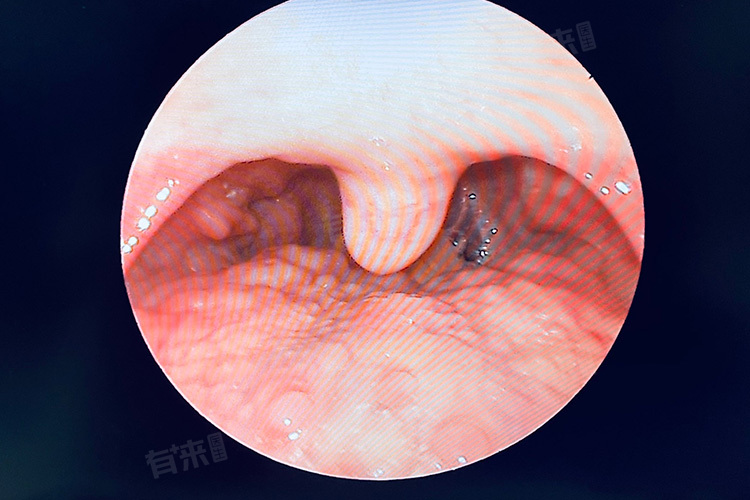

- 慢性感染灶:幽门螺杆菌感染可引发胃黏膜淋巴滤泡增生,其机制与细菌持续刺激黏膜相关淋巴组织有关。患者多伴反酸、嗳气等上消化道症状,胃镜检查可见胃窦部黏膜颗粒样增生,病理活检可检出幽门螺杆菌抗原,需与胃MALT淋巴瘤进行免疫组化鉴别。

- 慢性咽炎/反流性食管炎::长期吸烟、饮酒或接触粉尘等刺激物,可致咽部黏膜慢性炎症,淋巴滤泡代偿性增生。反流性食管炎患者因胃酸反流刺激咽喉部,亦可引发滤泡增生,伴反酸、烧心及咽部异物感,24小时食管pH监测可明确反流证据,需与胃食管反流病所致的Barrett食管鉴别。